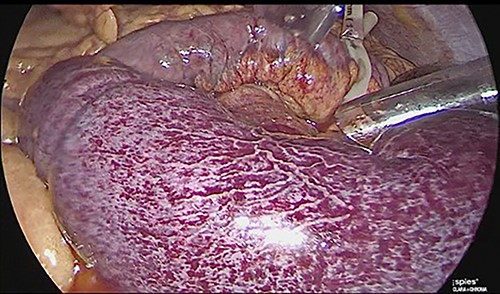

The patient was reoperated by laparoscopy, finding segmental thrombosis from 200 cm to 50 cm of the Treitz ligament, with edema and interloop free fluid without perforation (Figs 3 and 4). Lateral resection and entero–entero anastomosis were performed with manual stapler, subtracting 440 cm of intestine with adequate coloration. Later he was admitted to the Intensive Care Unit, treated with low molecular weight heparin at a full anticoagulation dose, maintaining an INR of 2 and a partial thromboplastin time of 80 s. He presented adequate evolution starting a liquid diet on the fourth postoperative day, new laboratories reported hemoglobin of 11 g/dl, 12 700 leukocytes/mm3, platelets 225 000/mcL, INR of 2. He was discharged on the fifth day with rivaroxaban treatment for 6 months.

Laparoscopic view of intestinal thrombosis and free fluid in the cavity.